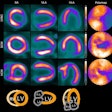

ISCT: CT is an ideal imaging modality for cardiometabolic screening